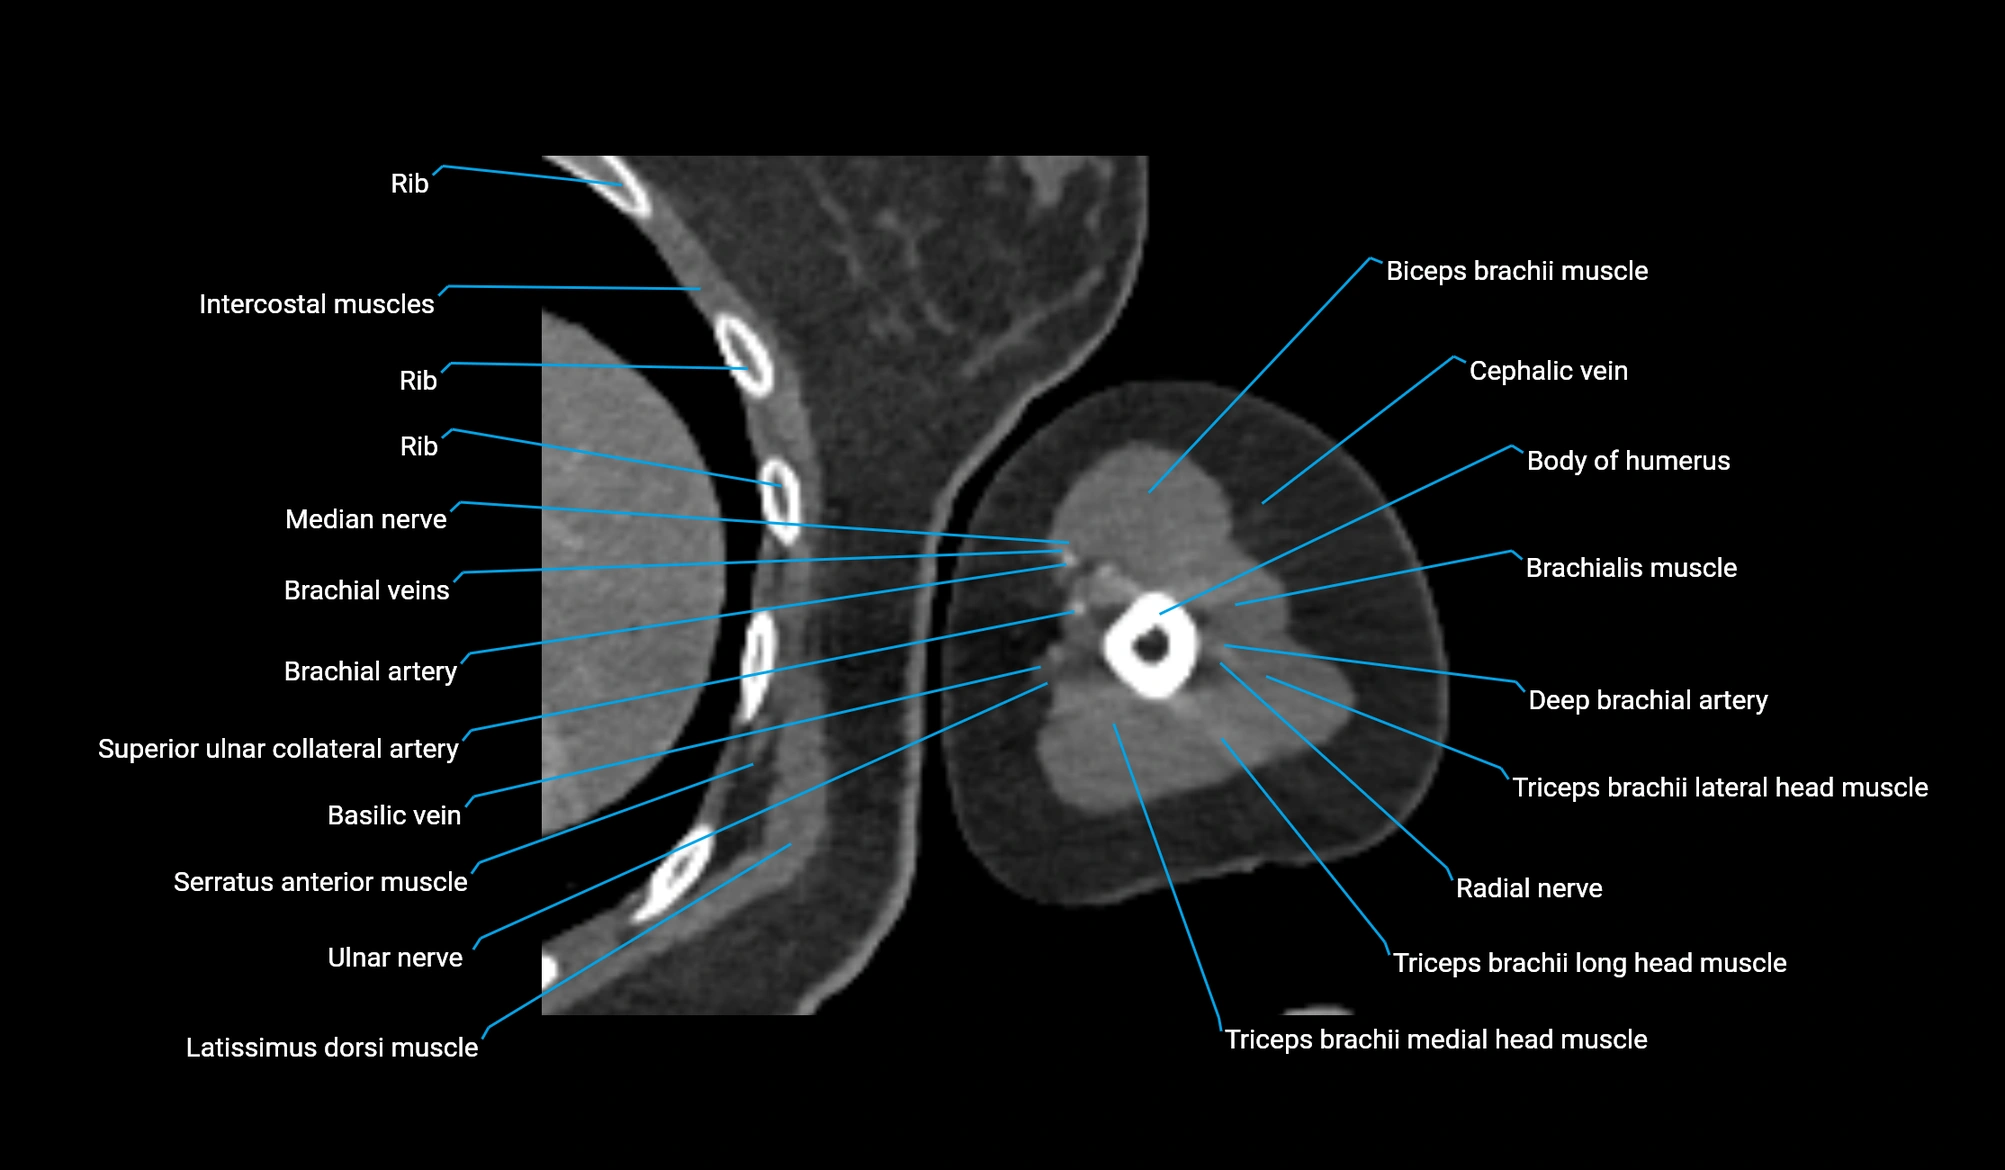

- Body of humerus

- Brachial artery

- Brachialis muscle

- Cephalic vein

- Deep brachial artery

- Lateral head of triceps brachii muscle

- Long head of triceps brachii muscle

- Medial head of triceps brachii muscle

- Median nerve

- Radial nerve

- Superior ulnar collateral artery

- Ulnar nerve